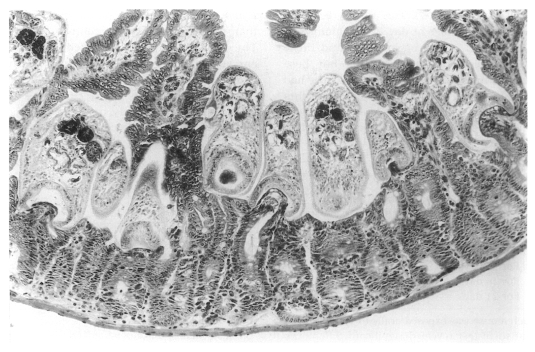

The in situ postures of G. seoi were shown in the small intestine of immunocompetent and immunosuppressed mice (Chai et al., 2001b). The purpose of immunosuppression was to enhance the survival of worms in the mouse intestine. The small intestines of G. seoi-infected immunocompetent mice (C3H/HeN) showed atrophy of the villi and hyperplasia of the crypts, with strong goblet cell hyperplasia along the mucosal epithelial layers (Fig. 22). Adult flukes of G. seoi were characteristically seen pinching and sucking the epithelial layer of villi with the oral suckers (Fig. 23). The appearance rate of flukes in tissue sections, however, was relatively low.

In contrast, in immunosuppressed C57BL/6 mice infected with G. seoi, numerous adult flukes were found sectioned (Fig. 24), pinching, sucking, and eating the root of villi in the small intestine (Chai et al., 2001b). Viewing from the postures of the adult flukes, their in situ behaviors could also be imagined. Most flukes contained fragments of host mucosal tissues within the oral suckers. Eventually displacement as well as complete loss of the villi occurred near groups of worms. A peculiar finding was that a few adult flukes were seen to have penetrated deep into the submucosa of the small intestine, just facing the serosa. These flukes also retained fragments of mucosal tissue within the oral suckers.

Goblet cell hyperplasia was remarkable along the villous epithelial layers, especially in the jejunum (Fig. 22) (Chai et al., 2001b). The adult flukes of G. seoi were characteristically seen pinching and sucking the epithelial layer of villi with their oral suckers (Fig. 23).

Effects of immunosuppression on the intestinal histopathology

The effects of immunosuppression on the intestinal histopathology elicited by G. seoi were also studied (Chai et al., 2001b). Uninfected C3H/HeN mice immunosuppressed with prednisolone revealed nearly normal contour of the small intestinal mucosa. By contrast, in C3H/HeN mice, immunosuppressed and infected with 300 metacercariae of G. seoi, the histopathological features were similar to those observed in immunocompetent mice. The destruction of villi adjacent to the flukes was, however, generally more severe than in immunocompetent mice. Many juvenile or adult flukes were seen sectioned occupying the intervillous spaces. They were seen pinching the root of the villus with the large oral suckers. Goblet cell hyperplasia was generally not remarkable. Villi adjacent to the flukes were destroyed, and some areas showed complete loss of villi. It was suggested that immunosuppression enhanced survival of many flukes in the host intestinal mucosa, and facilitated mechanical irritation by the flukes on the neighboring villi and crypts. Owing to immunosuppression, however, host systemic immune responses must have been compromised, and mucosal inflammation and pathology other than destruction of villi appeared to be generally mild.